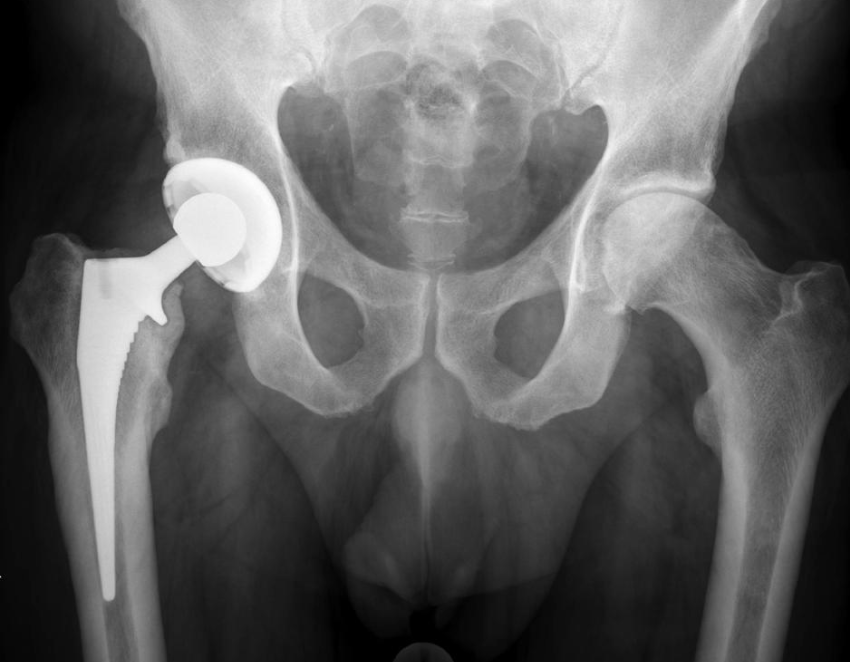

For our project, we are working on making hip implants better and safer for patients. One of the biggest issues faced in implants is the fretting corrosion of metal caused by micromotions at the taper interfaces of the prosthesis. This corrosion is affected by the way that the implant is assembled in the body. Our aim is to create a rig that will measure how a prosthesis is assembled and the amount of micromotion that occurs after applying an external axial force. This rig will then be used by surgeons for practice on assembling the hip prosthesis.

In 2014, more than 7 millions Americans had some kind of artificial orthopedic implant, such as artificial hips and knees. While the implants themselves are often state-of-the-art medical designs, they aren't perfect and can lead to later complcations. Two issues with the design of the modern hip prosthesis are at the stem-neck and neck-head taper interfaces, which both bear the risk of micromotions that can result in ongoing corrosion due to removal of the passive layer and ultimately cause implant fracture1 or even chronic inflammation and necrosis of periprosthetic soft tissues2.